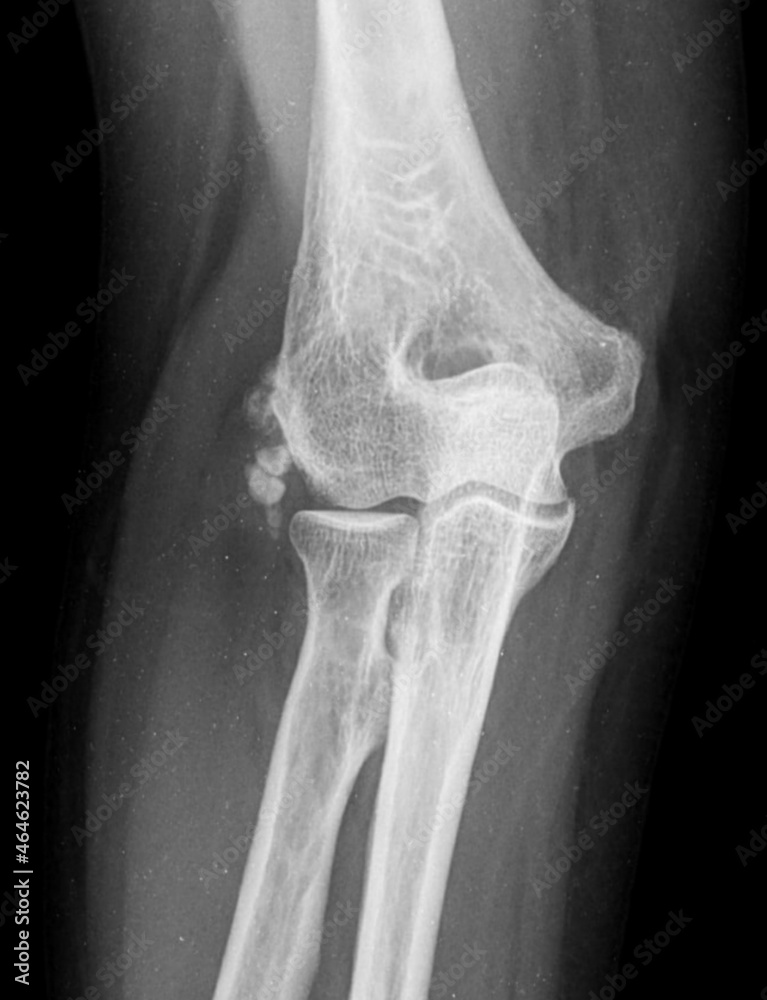

From stock.adobe.com

x ray of a Synovial chondromatosis elbow Stock Photo Adobe Stock Synovial Osteochondroma Elbow 2 because the dominant elbow is more commonly. synovial chondromatosis (osteochondromatosis or synovial chondrometaplasia) also known as reichel. osteochondromas are benign chondrogenic lesions derived from aberrant cartilage from the perichondral ring that. Synovial chondromatosis can arise in any joint in the body, but most commonly occurs in the knee. synovial chondromatosis (sc) is a benign uncommon condition. Synovial Osteochondroma Elbow.